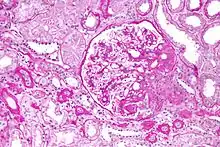

Гіпоальбумінемія також може бути частиною нефротичного синдрому, при якому значна кількість білка втрачається з сечею через ураження нирок. У нормальних умовах через клубочок втрачається менше 30 міліграм альбуміну на день.[2] При нефротичному синдромі втрата білка може досягати 3,5 г протягом 24 годин, більша частина якого — альбумін, що й призводить до гіпоальбумінемії.[2] У дітей нефротичний синдром, як правило, є первинним процесом, який значною мірою є ідіопатичним, хоча зі зниженням вартості та збільшенням доступності секвенування цілого екзому ідентифікується все більше генетичних причин. Біопсія нирок дозволяє діагностувати хворобу мінімальних змін, мембранопроліферативний гломерулонефрит або вогнищевий сегментарний гломерулосклероз, що призводять до нефротичного синдрому у дітей.[5] У дорослих, нефротичний синдром, як правило, є вторинним процесом. Його причини можуть бути різноманітними, такі як токсини, ліки, важкі метали, аутоантитіла, постінфекційні комплекси антитіл або імунні комплекси, що утворюються при злоякісних новоутвореннях, таких як мієломна хвороба.